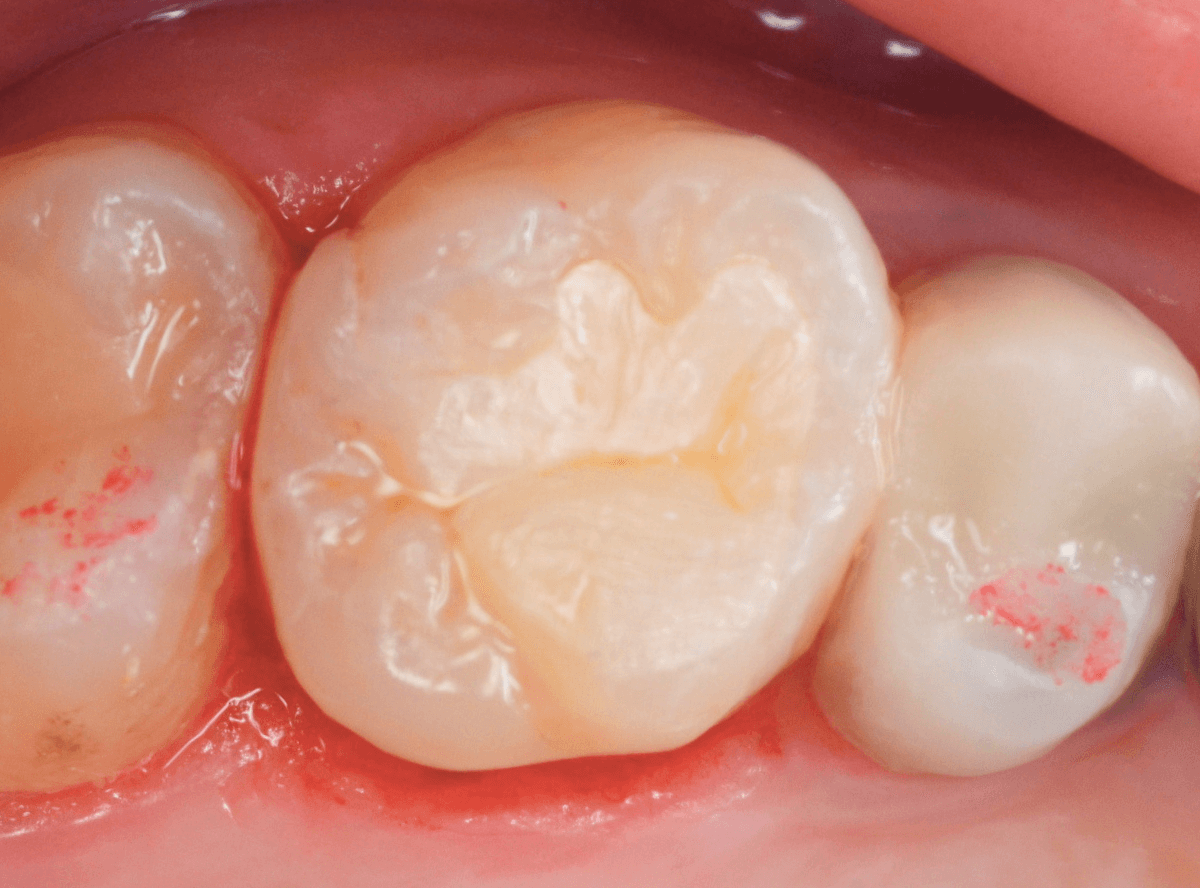

治療後の状態です。

ジルコニア・インレーはE-MAX・インレーより審美性に劣るのですが、患者さんにもご満足いただける仕上がりになり、ホッとしました。